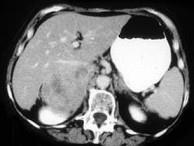

问题 女,37岁,向心性肥胖2月,请结合所提供图像,作出诊断 ( )

选项 A、右肾上腺嗜铬细胞瘤 B、右肾上腺增生 C、右肾上腺腺癌 D、右肾上腺转移瘤 E、右肾上腺腺瘤

答案 C